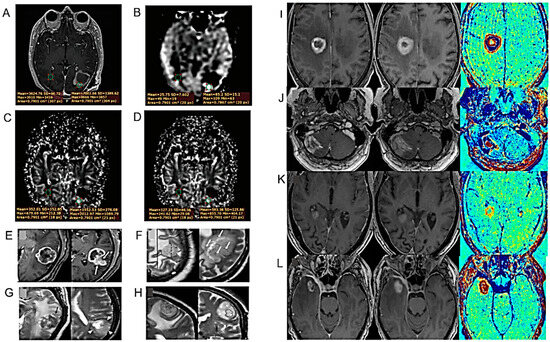

| T1-relative CBV effectively diagnosed progressive lesions in patients with HGG, suggesting the potential role of T1-PWI as a valid alternative to the traditional T2*-PWI. | 45 MRIs of 34 patients with proved HGG. | [23] |

| ASL and DSC have similar diagnostic accuracy. | 115 BT patients who underwent both ASL and DSC perfusion in the same 3T MRI scanning session. | [36] |

| Semi-quantitative analysis using SWI may contribute to the differential diagnosis between HGG recurrence and radionecrosis, but cannot identify BM. | 56 patients with BM and 42 patients with HGG. | [37] |

| Study of an analytical qualitative algorithm to differentiate HGG from BM. | 36 patients with histologically proven HGG or solitary BM matched by size and location. | [38] |

| Use of the tissue permeability and microcirculation parameters Ktrans, Kep, IAUC to differentiate PT from TM. | 34 patients with HGG. | [43] |

| Unlike the quantitative measurements of DSC and DCE perfusion maps, their qualitative assessment has low inter-examinator agreement. | HGG patients who underwent re-resection of a new enhancing lesion on post-treatment 3T MR examination including DWI, DCE and DSC sequences. | [45] |

| After DKI of the peritumoral edema area, significant differences between grade III and IV gliomas. DKI parameters correlate with Ki-67. | 51 patients with gliomas undergoing DKI scans before surgery. | [55] |

| The number of tumor blood vessels permits differentiating IDH1 mutations | 44 glioma patients [16 with IDH1 mutant-type (IDH1-MT), 28 with IDH1 wild-type (IDH1-WT)]. | [62] |